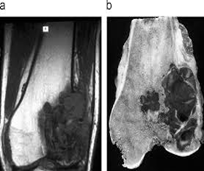

2. Resonancia magnética

Examen histopatológico

El examen histopatológico, es decir, el examen de tejidos en un microscopio, se lleva a cabo sobre una biopsia o porción de tejido tras la extirpación de todo el tumor por cirugía. Sólo la evaluación histopatológica del tumor revelará si el tumor es un sarcoma óseo y, en su caso, de qué tipo. También proporcionará el “grado de malignidad”, esto es, una clasificación de la agresividad de las células del cáncer.

Se usa una amplia gama de técnicas de adquisición de imágenes para poder ver dentro del cuerpo y determinar el alcance de un sarcoma óseo y establecer la presencia o ausencia de enfermedad metastásica distante.